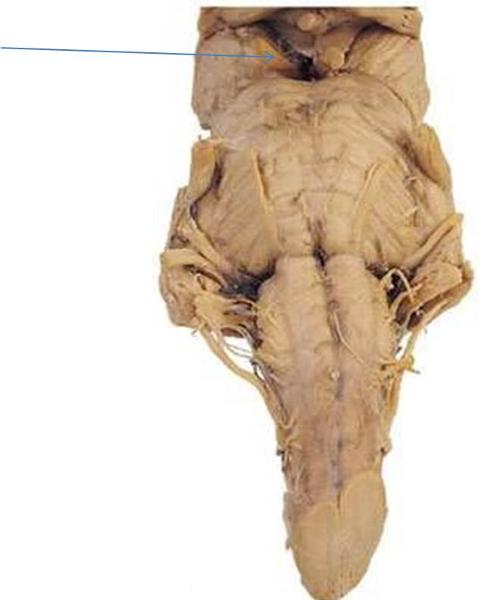

Sheep brain – external anatomy (ventral) | Hypoglossal nerve, Abducens …

Print Neuro Lab Block I- Brain Stem Gross Anatomy flashcards | Easy …